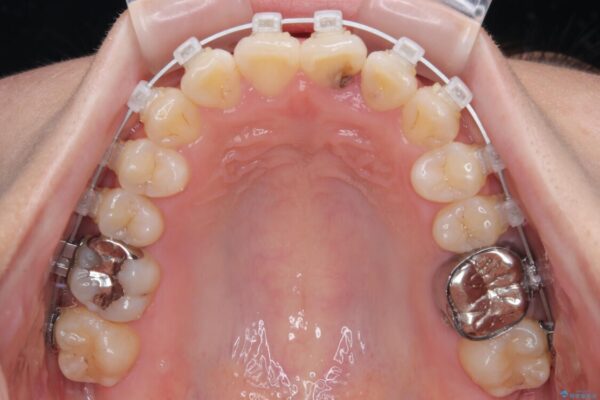

治療途中

• 前歯のねじれ・ガタガタを10か月で改善!20代女性の矯正治療|クリアブラケットでむし歯になりにくい歯並びへ改善 治療途中画像